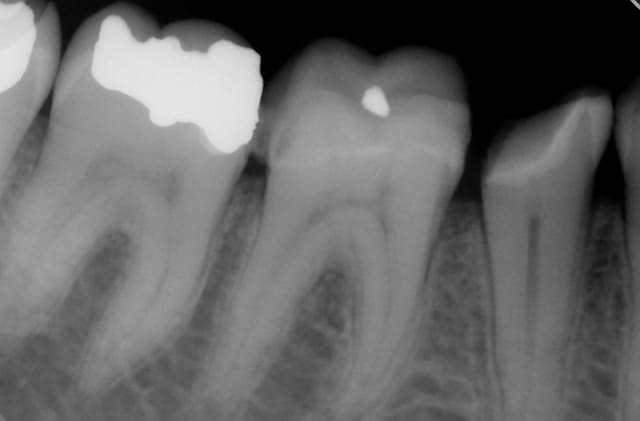

Voilà ce patient a consulté en Juillet pour une douleur à la mastication. Je regarde la radio, belle pêche sous les racines, en bouche, une fêlure traversant la dent dans le sens MD. A votre avis que faire dans ces cas et comment évaluez vous la réussite ou non de l'endo - CCC dans ces cas? Il n'avait aucune douleur quand j'appuyais transversalement de sur la moitié linguale ni sur la moitié vestibulaire (vers l'extérieur de la dent, pour "séparer" les dent).

J'ai émis de grosses réserves sur la pérennité du traitement et il a tout de même voulu procéder (j'avais même recommandé l'extraction, je ne travaille pas en France et quand le patient paie tout de sa poche c'est dur de "tenter", si ça merde y'a de grandes chances qu'il se retourne contre vous).

Bref je fais l'endo, et lisant de plus en plus de choses sur le sans-tenon (surtout le risque de fracture supérieur qu'il engendrait par perte de substance dentinaire) je me suis lancé dans un "Nayyar" core, compo descendant dans les entrées canalaires et par dessus une CCC.

Ci-joint les radios.